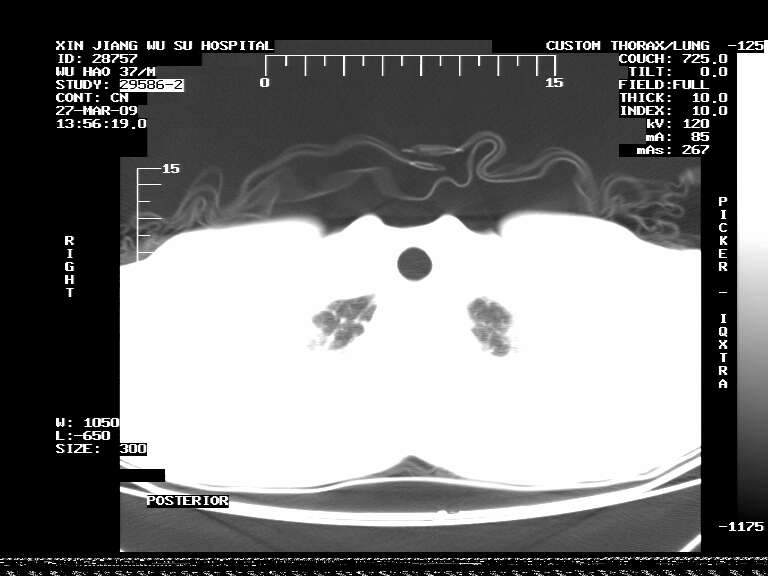

标题: CT19113:体检胸透发现阴影,CT图像。

男,37岁,体检胸透发现阴影。

患者体检发现 无症状 左肺下叶占位,边缘模糊,可见血管聚束、分叶、胸膜牵拉,增强呈不均匀性强化。 首先考虑左肺下叶周围型肺癌,建议穿刺活检。

患者体检发现 无症状 左肺下叶占位,边缘模糊,可见血管聚束、分叶、胸膜牵拉,增强呈不均匀性强化。 首先考虑左肺下叶周围型肺癌,建议穿刺活检。支持!

左肺下叶见一结节病变,边缘欠清不光滑,与胸膜粘连且胸膜局限性增厚,注药后呈环形强化,动脉期壁呈明显点环状强化,静脉期壁强化减低,中心密度低无强化,灶周无明显的卫星灶和水肿区(晕征)---考虑周围性肺癌,不除外感染性病变,建议穿刺活检。

左肺下叶软组织病灶,密度较高,内见点状钙化,其周围见子灶,邻近胸膜扁平样增厚.c+病灶强化明显,中心强化弱.诊断:左肺下叶结核瘤.